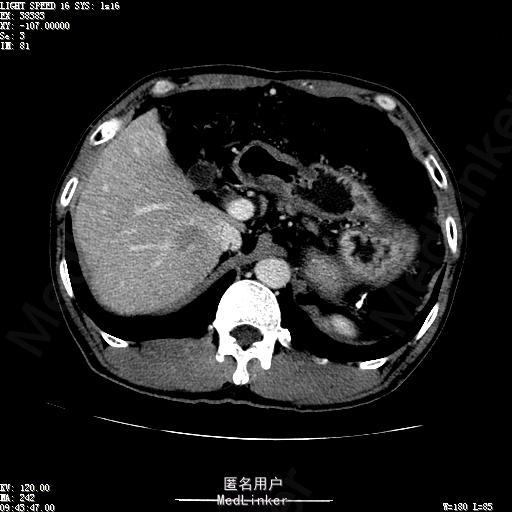

查体:体温36.4℃,脉搏76次/分,呼吸18次/分,血压110/70mmHg。神志清晰,发育正常,营养中等,体位自如,表情安静,慢性病容,检查合作。皮肤粘膜颜色正常,无瘀点、紫癜,有肝掌,无蜘蛛痣,无水肿,毛发的生长与分布正常。浅表淋巴结浅表淋巴结未触及肿大。无巩膜黄染,结膜正常。口唇红润,粘膜正常,舌正常,牙龈正常,扁桃体无肿大,无咽部充血。颈部外形对称,颈静脉正常,肝颈静脉回流征阴性,气管居中。甲状腺正常,无颈部血管杂音。胸部形态正常,呼吸运动平稳规律,无呼吸困难,肋间隙正常。触诊语颤正常,无胸膜摩擦感,肺下界位于右锁骨中线第六肋间。呼吸音正常,未闻及干湿啰音,无胸膜摩擦音。无心前区隆起,心尖搏动正常,心率:76次/分,心律齐,心音正常,无杂音,无心包摩擦音。无大动脉及周围血管征,无奇脉及交替脉,无水冲脉,无枪击音,腹型对称,无腹壁静脉曲张,未见胃肠型及蠕动波,无瘢痕,脐部正常。无压痛,无反跳痛,无腹肌紧张,无腹部包块。肝未触及,Murphy征阴性,脾未触及,肾未触及,无移动性浊音。无肝区叩击痛,无肾区叩击痛,无脾区叩击痛。肠鸣音正常4次/分,无气过水声。外阴及肛门:未查。四肢正常,关节正常,无下肢水肿,无下肢静脉曲张,无杵状指趾。 辅助检查:彩超:肝表面欠光滑,肝内占位5.2*5厘米 ct如下图

诊断:乙肝肝硬化 代偿期 原发性肝癌。 患者病史明确,目前化验转氨酶轻度升高,说明有活动性肝损伤,白蛋白降低提示肝脏合成代谢功能下降,AFP从一年前至今逐渐升高,提示活性肿瘤细胞增多。CT所见明确诊断肝癌,并有周围卫星灶,应近期行TACE治疗。 处置:DSA下肝动脉造影及TACE 手术简要经过:患者平卧位,术区皮肤消毒,铺手术巾,2%利多卡因局麻后,Seldinger法穿刺右股动脉,入血管鞘,5F猪尾管腹主动脉造影,超滑导丝yidao5F RH管腹腔干、肠系膜上动脉、左肾动脉分别造影,腹腔干造影时,见肝右叶7-8处小结节样肿瘤染色,未见外凸生长较大病灶染色。微导管超选肝右动脉注入三氧化二砷碘油混悬液10毫升,横结肠遮挡部位见较大病灶有伞状碘油沉积。复查造影未在见肿瘤染色,拔出导管和血管鞘,穿刺处压迫止血,加压包扎。术毕。

患者术后8天来,无不适,无发热,无腹痛和腹胀,无恶心呕吐,食欲睡眠好,尿便正常。 查体:神志清,巩膜无黄染,心肺听诊无异常,腹软,无压痛,肝脾肋下未触及,移动性浊音阴性,双下肢无浮肿。 复查化验结果:丙氨酸氨基转移酶 116 U/L、天门冬氨酸氨基转移酶 41 U/L、胆碱酯酶 1995 U/L↓、总蛋白 56.3 g/L、白蛋白 25.9 g/L。白细胞计数 5.8 10^9/L、红细胞计数 3.18 10^12/L、血小板计数 175.0 10^9/L、*血红蛋白 83 g/L、血小板分布宽度 15.7 、血小板压积 0.175 %、*红细胞压积 24.6 %、平均红细胞血红蛋白 26.1 pg、平均红细胞血红蛋白浓度 337.0 g/L、平均红细胞体积 77.5 fL、平均血小板体积 10.0 fL、嗜碱性粒细胞百分比 0.4 %、嗜碱性粒细胞数量 0.02 10^9/L、中性粒细胞百分比 70.4 %、中性粒细胞数量 4.10 10^9/L、嗜酸性粒细百分比 2.1 %、嗜酸性粒细胞数量 0.12 10^9/L、单核细胞百分比 12.2 %、单核细胞计数 0.7 10^9/L、淋巴细胞数量百分比 14.9 %、淋巴细胞计数 0.9 10^9/L。甲胎蛋白 23564.00 ng/mL 患者术后第8天开始行FOLFOX6化疗。CT上可见明显碘油沉积,术后甲胎蛋白下降治疗有效。嘱患者术后必须定期复查